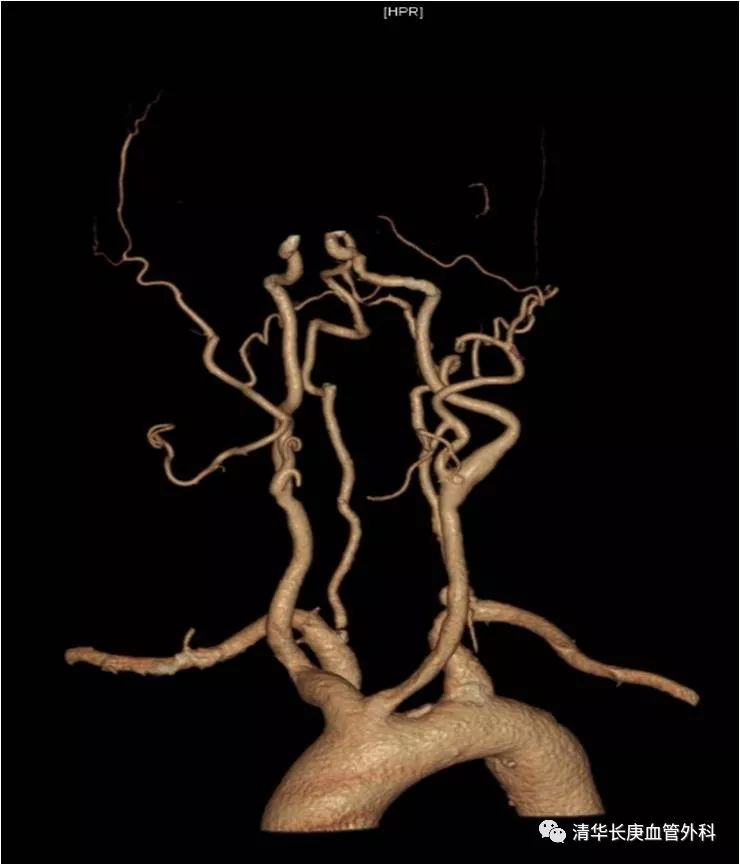

赵克强副主任医师,以典型病例录播形式,向学员们分享了弓上动脉病变的治疗,包括锁骨下动脉闭塞、复杂弓型颈动脉支架的入路建立、多发病变、串联病变的治疗策略,以及弓上病变围术期管理、术中技巧、常见并发症及预防措施;学员们积极踊跃、畅所欲言、交流心得,对弓上病变的诊治有了进一步的认识、体会。

锁骨下动脉闭塞,长鞘+椎管+CXI+V18同轴系统通过病变

双导丝技术

不友好弓型的入路建立